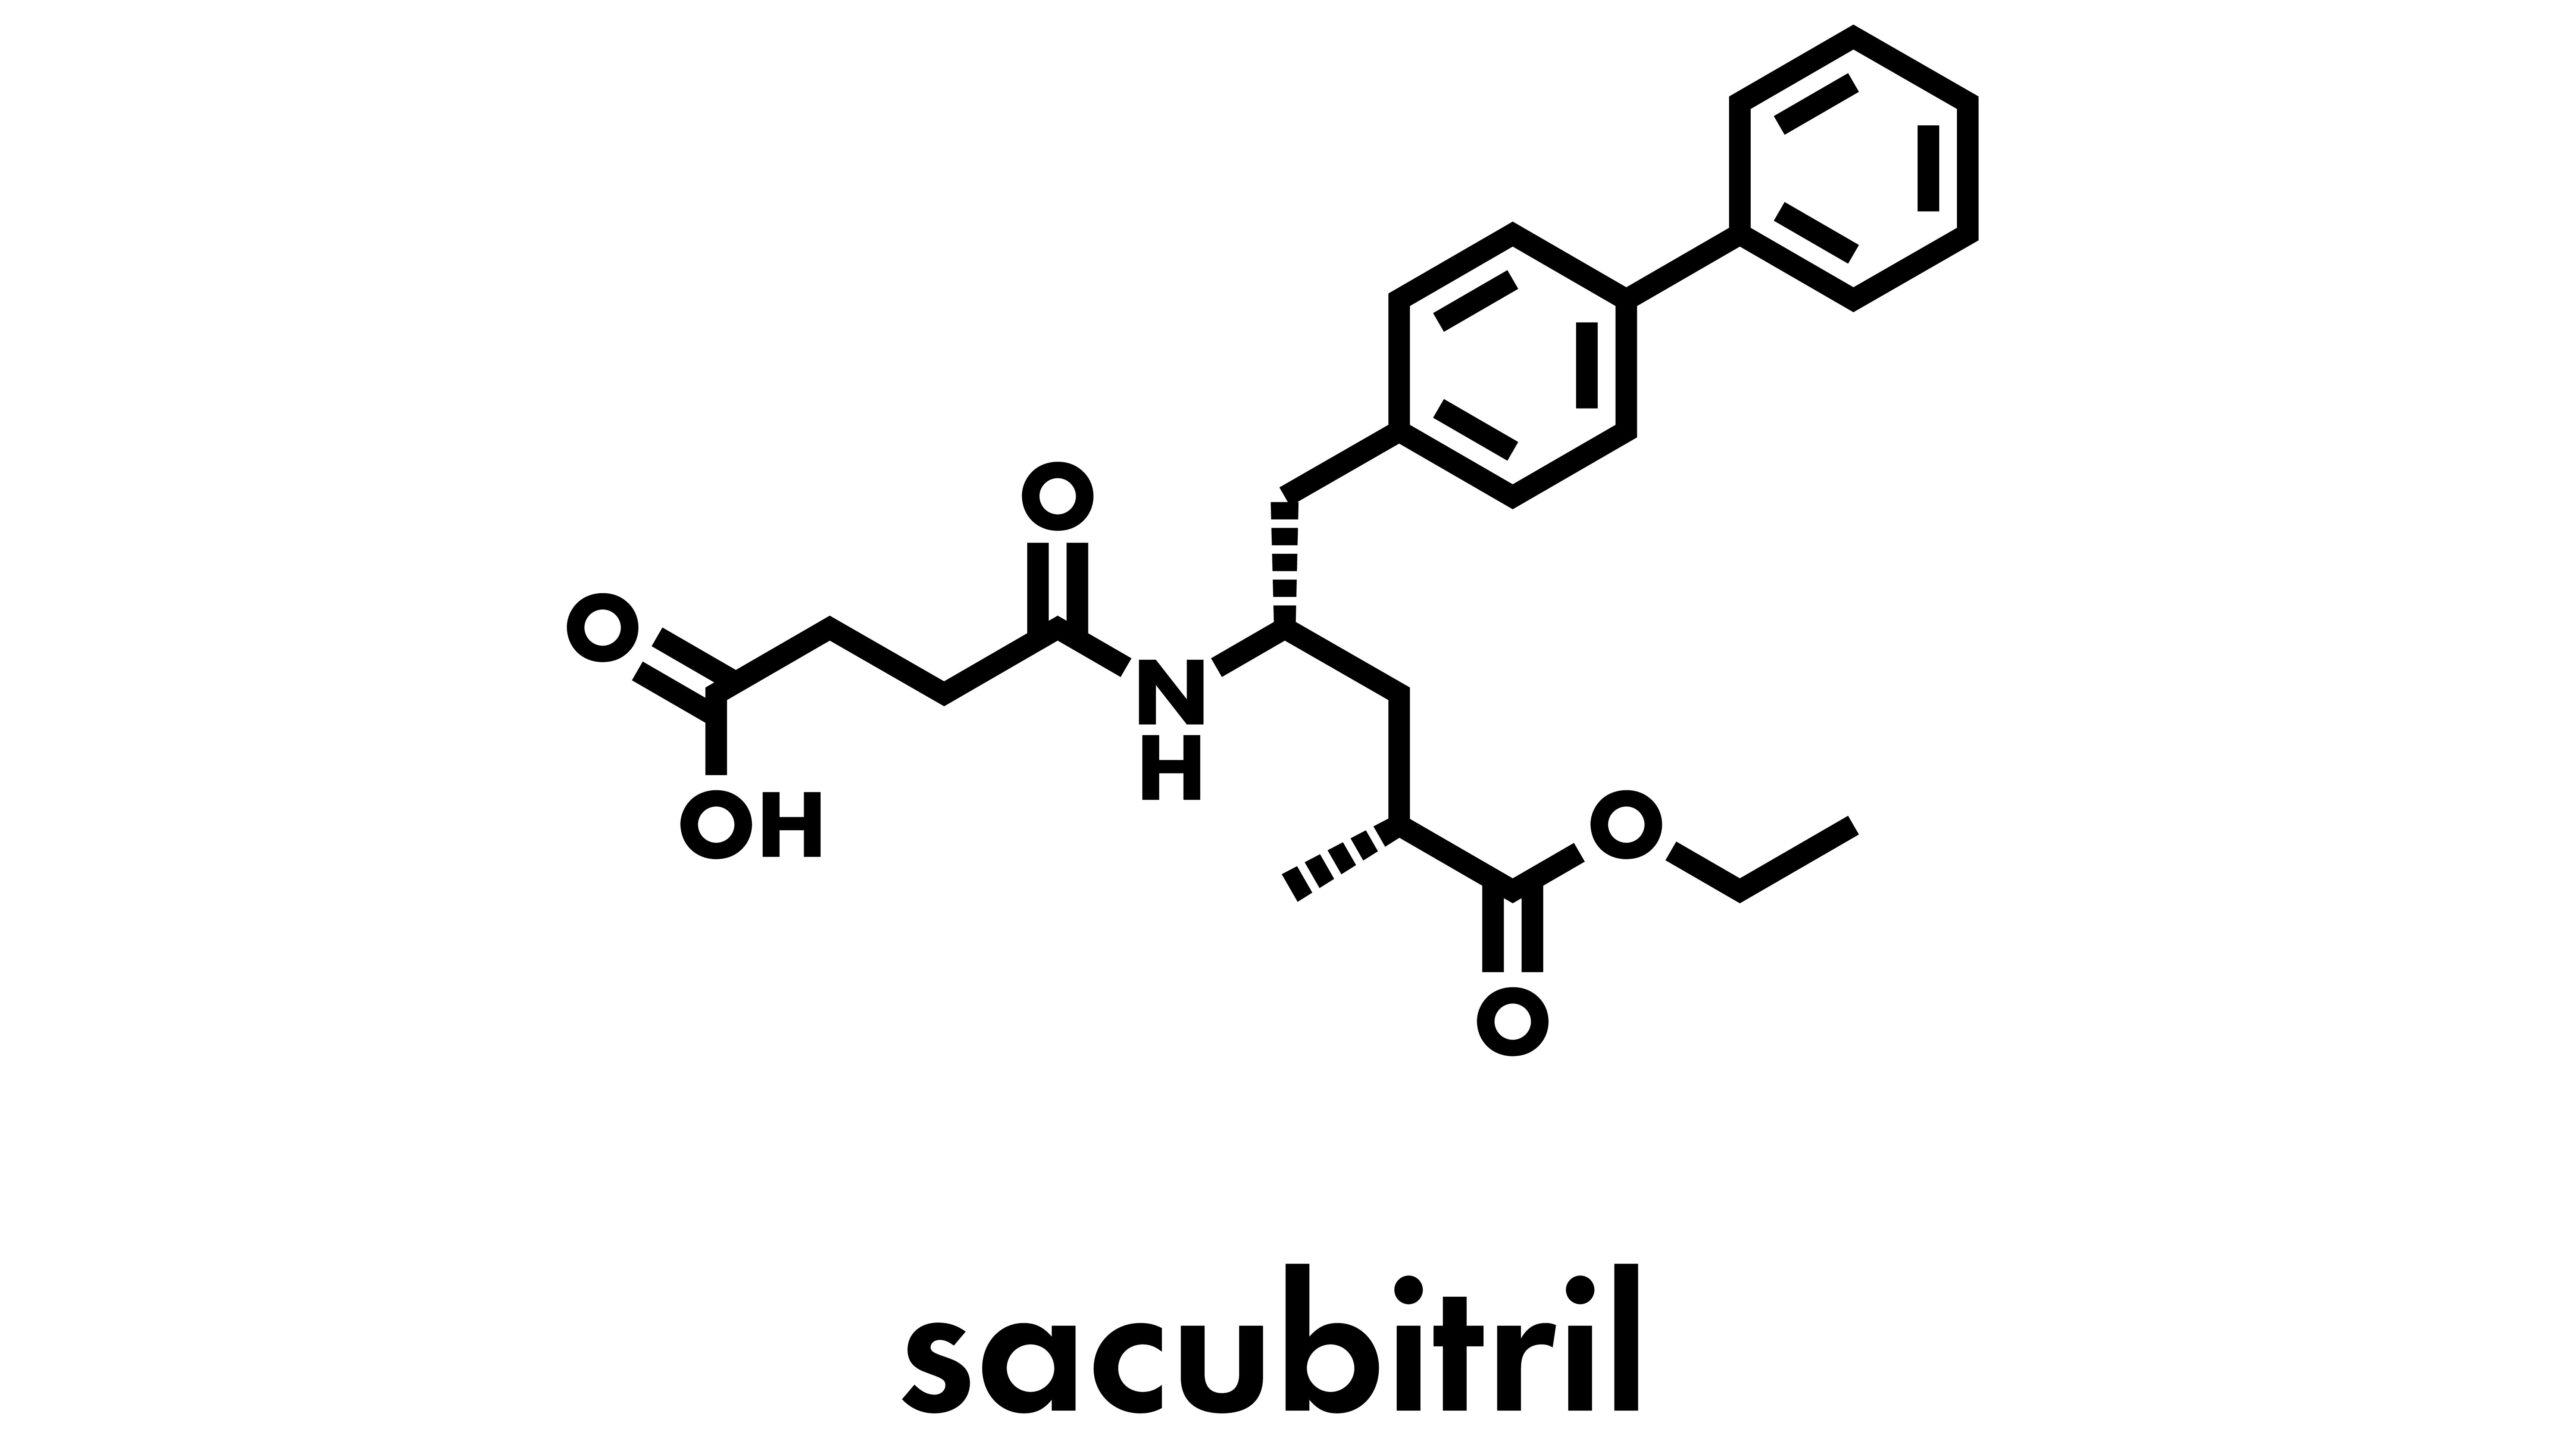

Sacubitril/valsartan therapy improved outcomes compared with enalapril in heart failure with preserved ejection fraction.Patrick DalyCardiology | July 13, 2023